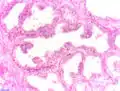

Invasion périneurale par un adénocarcinome prostatique. HE, x400

Anatomopathologie

Le cancer entreprend la portion périphérique de la glande, au contraire de l'hypertrophie prostatique bénigne qui intéresse la zone centrale, périurétrale.

Des études ont montré que des fibres nerveuses (issues de prolongements d'axones de neurones préexistants dans le système nerveux périphérique) peuvent infiltrer les adénocarcinomes de la prostate, contribuant aux phases précoces du développement tumoral et à sa progression[49]. Par ailleurs, le système parasympathique cholinergique régule l’invasion tumorale et l'émission de métastases, en activant le récepteur muscarinique de type 1 (Chrm1) du microrenvironnement tumoral[50]. En 2019, le même laboratoire découvre que des neurones peuvent être créés au sein même du microenvironnement tumoral[51]. Ils y sont produits par des cellules neurales souches provenant du cerveau et acheminées par la circulation sanguine. En effet, on trouve dans les tumeurs, des cellules exprimant une protéine, la doublecortine (DCX), généralement exprimée par les cellules progénitrices neuronales, lors du développement embryonnaire et, chez l’adulte, dans les deux zones du cerveau où les neurones se renouvèlent : le gyrus denté dans l’hippocampe et la zone sous-ventriculaire. Une corrélation entre sévérité du cancer et taux de cellules DCX+ est observée. Il a été mis en évidence chez la souris, que la présence de tumeur est associée à des anomalies de perméabilité de la barrière hématoencéphalique de la zone sous-ventriculaire, permettant la migration dans le sang de cellules DCX+ depuis cette zone sous-ventriculaire. Ces cellules se retrouvent dans la tumeur et les nodules métastatiques où « elles se différencient en neuroblastes puis en neurones adrénergiques producteurs d’adrénaline » ce qui pourrait favoriser la vascularisation et le développement des tumeurs[52].